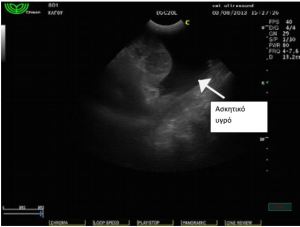

Στον υπέρηχο κοιλίας βρέθηκε μάζα σπηλαιώδης, η οποία

ξεκινούσε από τον σπλήνα και καταλάμβανε μέρος της πρόσθιας

κοιλίας καθώς και παρουσία ασκητικού υγρού. Το ήπαρ φαινόταν

φυσιολογικό χωρίς απώλεια της δομής και του σχήματός του.